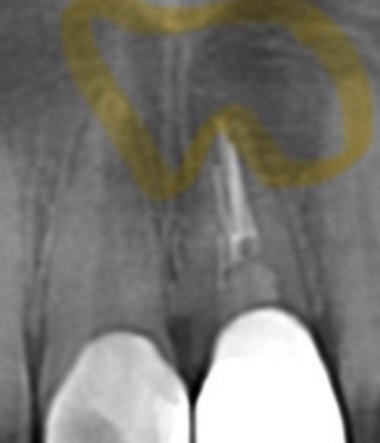

術後6ヶ月時点 レントゲン

| 治療後経過 | 6ヶ月経過 パノラマレントゲンにて患部の骨の回復が見られた。打診痛、自発痛共に無く経過良好。 |

| 主訴 | 左上前歯が痛くて歯茎が腫れている。3年ほど前に神経治療をした。 |

|---|---|

| 所見 | パノラマレントゲンにて左上1番2番に透過像が確認され、根尖相当部歯肉にフィステルあり。また排膿も伴う。打診痛、自発痛あり。 |

| 診断 | 左上1.2部 慢性根尖性歯周炎 |

| 治療内容 | 感染根管処置を行い根管内を無菌化し、貼薬を行った後、マイクロスコープ下にて歯根端切除術を行った。 |

| 治療期間 | 1ヶ月 |

| 治療費用 | 100,000円 自由診療 |

| リスク・副作用 | 病変が消失しないことがあります。 |